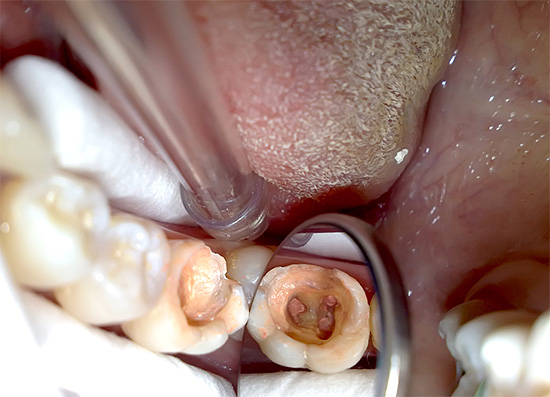

Foto di un dente con polmonite gangrenosa cronica: un'ombra grigia malsana è chiaramente visibile:

Quando si esamina un dente, la sua tinta grigia colpisce di solito in presenza di una cavità cariata che si estende in profondità nella bocca dei canali radicolari. Quando si sondano, si nota la presenza di una grande quantità di dentina ammorbidita cariata e la penetrazione profonda dall'estremità acuta della sonda nella bocca dei canali radicolari è spesso dolorosa, sebbene a volte si verifichi dolore quando viene uccisa una parte della polpa radicolare.